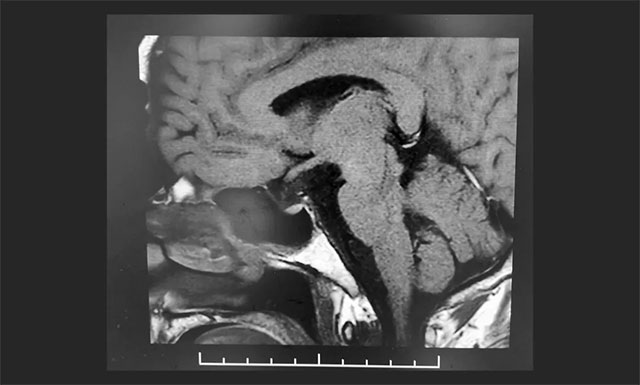

▲ 术后影像显示肿瘤被切除

术后,根据病理检测,患者确诊为颅咽管瘤。患者视力较前术明显改善,未出现尿崩,垂体激素无异常,精神状态稳定,目前正在康复中。李士其教授叮嘱患者出院后仍需定时复查。